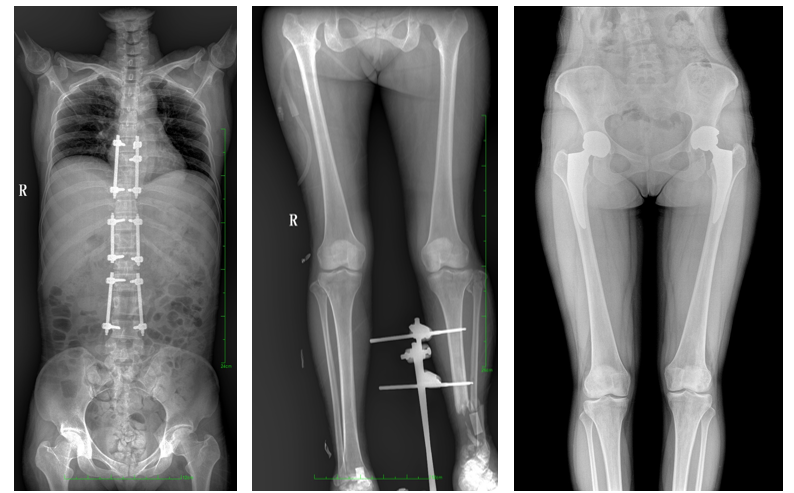

大视野平板动态DR临床影像

PLX8600大视野平板动态DR可在低辐射剂量下获得患者站立位、卧位的高质量影像。搭载自主研发的图像均衡处理系统,能够很好的均衡人体不同厚度组织的影像,视野大,图像清晰,层次丰富。